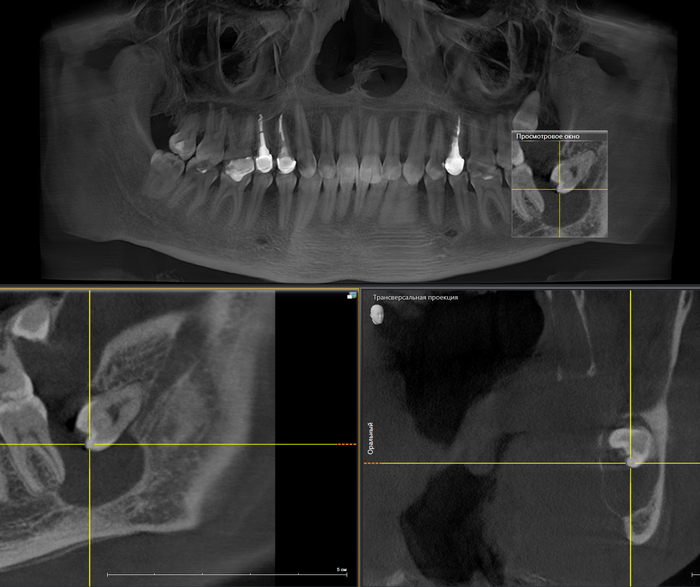

На прием пришла девушка с пожеланием восстановить удаленный ранее в другой клинике зуб на верхней челюсти справа. Ну что ж, без проблем. Направляю пациентку на компьютерную томографию для оценки ситуации. И вдруг я вижу «её» – притаившуюся в пазухе омерзительную восьмерку, которая, противно ухмыляясь, смотрит прямо на меня.

Кроме того, что она сама по себе противная, так еще она успела навредить 7му зубу.

Красным пунктиром отмечено разрастание фолликулярной кисты, которая распространилась в область корней зуба по соседству.

Контрольный снимок после удаления:

На всё про всё ушло минут 25, а вы говорите стационар

После снятия швов пациентка была направлена к терапевту для принятия решения о необходимости лечения каналов в 7м зубе. После проведения холодовой пробы стало понятно, что зуб живой, поэтому необходимости в его лечении на данный момент нет. Оставляем под пристальным наблюдением.